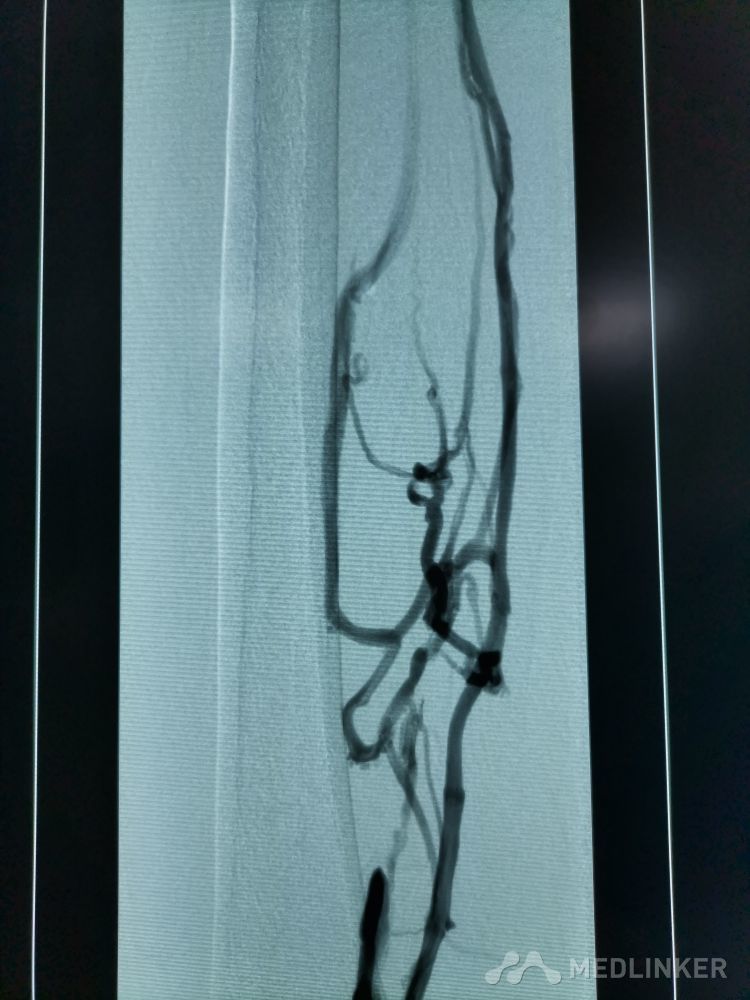

重视髂静脉压迫综合征。不同的临床表现,相同的病因,均为髂静脉压迫所致。第一例,表现为下肢静脉曲张伴溃疡,造影证实,髂静脉支架置入后解决。第二例,表现为左侧髂股静脉血栓,置管溶栓并髂静脉支架置入开通血管。第三例,下肢深静脉血栓后遗症,外院已行髂静脉支架置入,但皮肤营养情况仍持续加重,开通股浅 ,可见病变局部异常坚硬。精准施治,对症下药。